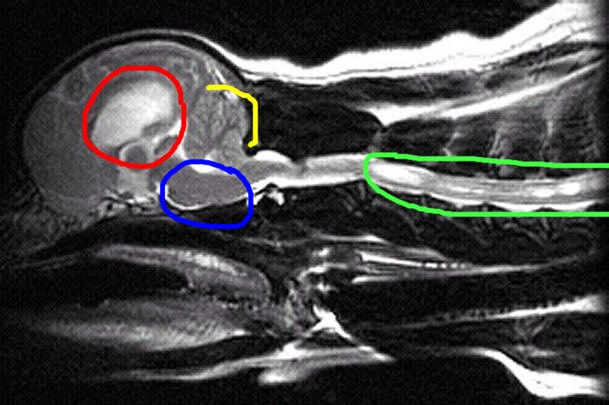

How do I know if my dog has Syringomyelia?

The only way to confirm a diagnosis is by MRI (Magnetic

Resonance imaging). This is essentially a picture of the water

content of the body presented in a series of slices (like a loaf

of bread). Nervous tissue, which contains a lot of water, is not

imaged by x-rays but is shown in great detail by MRI. The

syringomyelia can be easily-visualized as a pocket of fluid

within the spinal cord. In severe cases the syrinx is so wide

that only a thin rim of spinal cord remains.